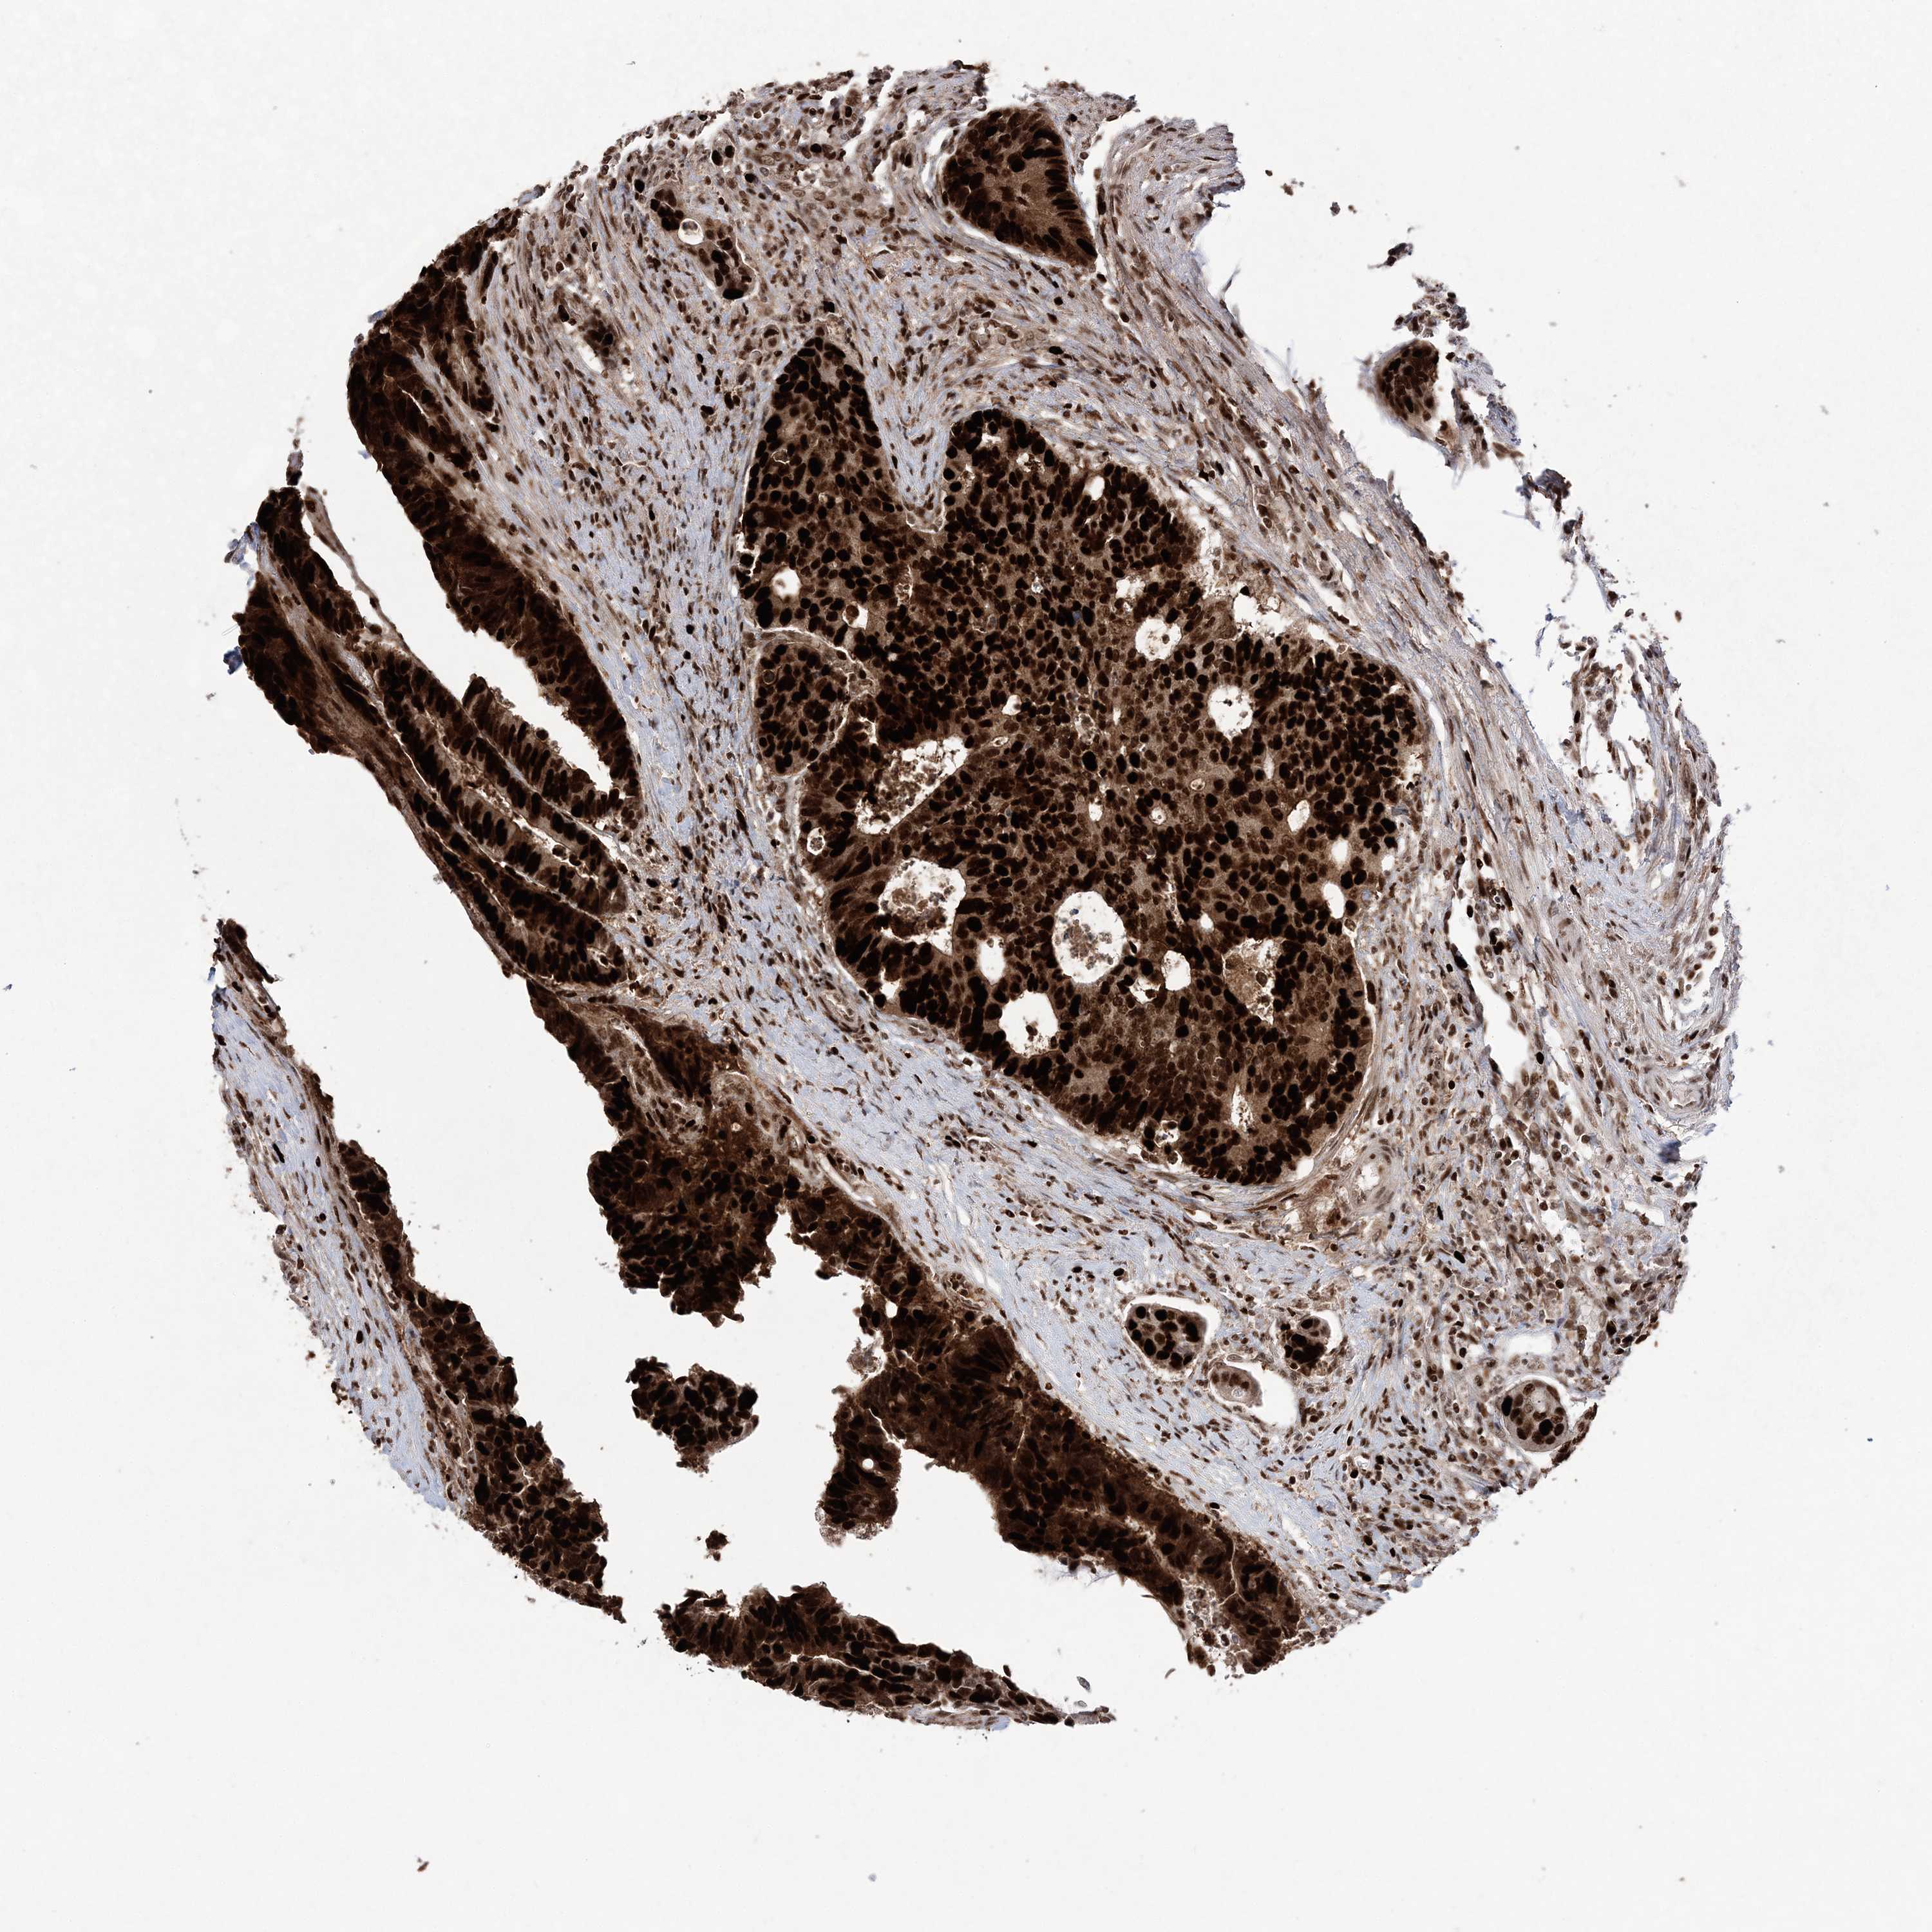

CANCER COLORECTAL CANCER Show tissue menu

ANTIBODIES

AND

VALIDATION

Colorectal cancer

Human cancer

Colon adenocarcinoma